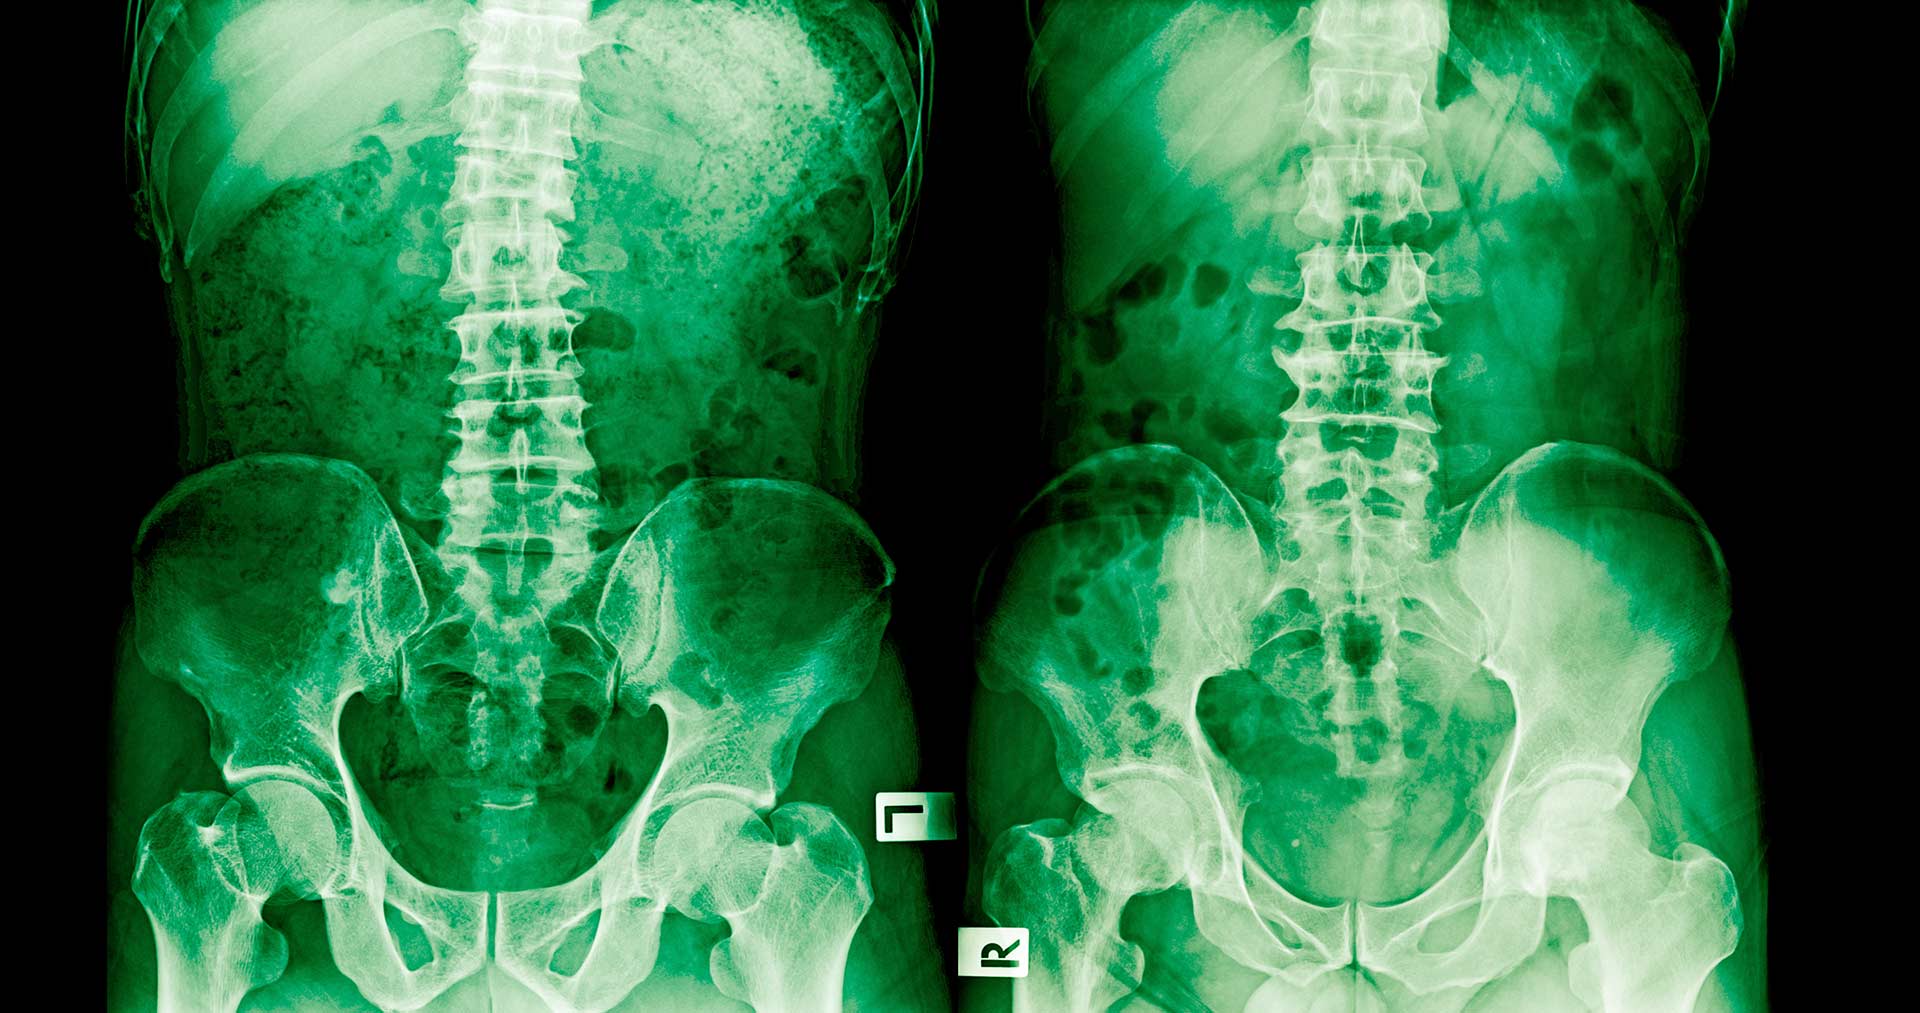

The majority of spinal cord injuries resulting from medical negligence are the result of inappropriate diagnosis or errors during neurosurgery. Neurosurgeons are the most highly trained of all surgical specialists. A mistake made during any part of a neurosurgical procedure can result in damage to a critical part of the brain or nerve bundles in the spinal cord.

The neurosurgeon is responsible for every component of diagnosis and care of the patient, including radiology, MRI and diagnostic tests, preoperative care, anesthesia, the surgical team and postoperative treatment. A mistake at any point in treatment can have devastating consequences.